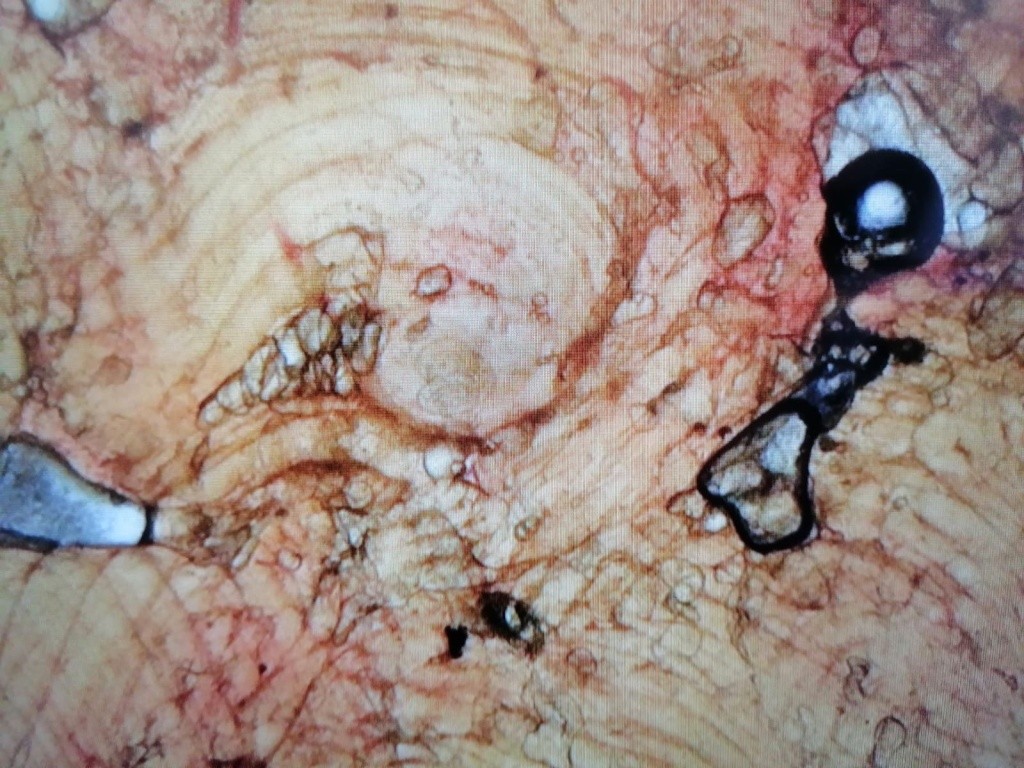

На фото личинки Trichinella spiralis в капсуле.

Фото: ГБУ РМЭ «Медведевская райСББЖ»